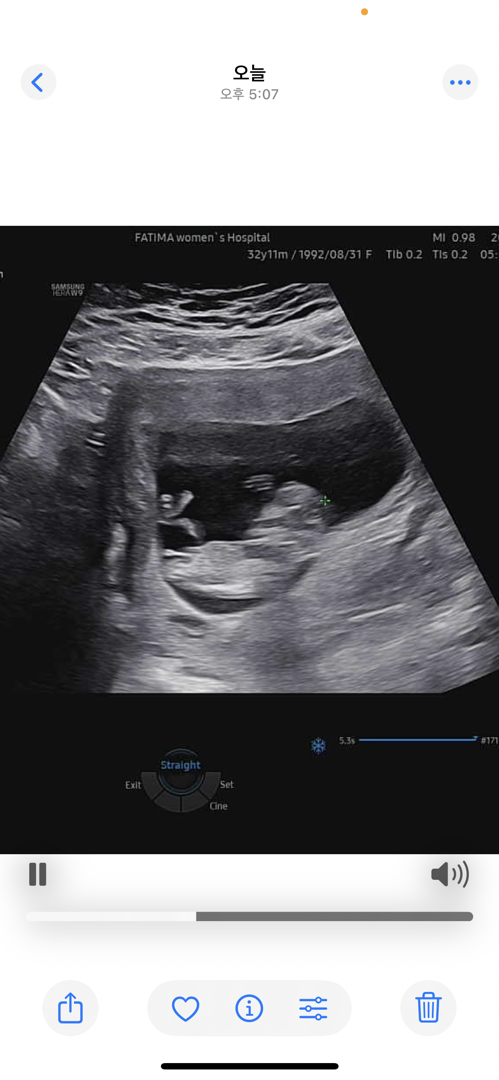

성별이 넘 궁금해용 11주 4일 ! ㅜㅜㅜ

넘 이르지만 ㅜㅜ 참견 해주세용